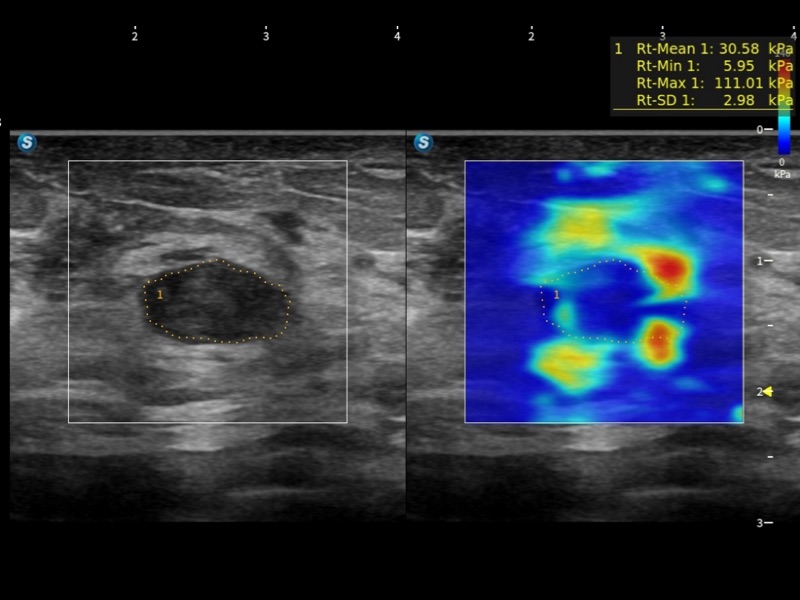

作为开立医疗全新打造的超高端旗舰超声产品,从探头抬起唤醒开启扫查到多维探头发射接收,通过先进的场成像发射、自适应聚合重建等技术,基于RF Data原始射频数据在图像生成、高端功能等方面实现突破,提供多科室综合临床解决方案。

独有场成像发射技术

自适应聚合重建技术